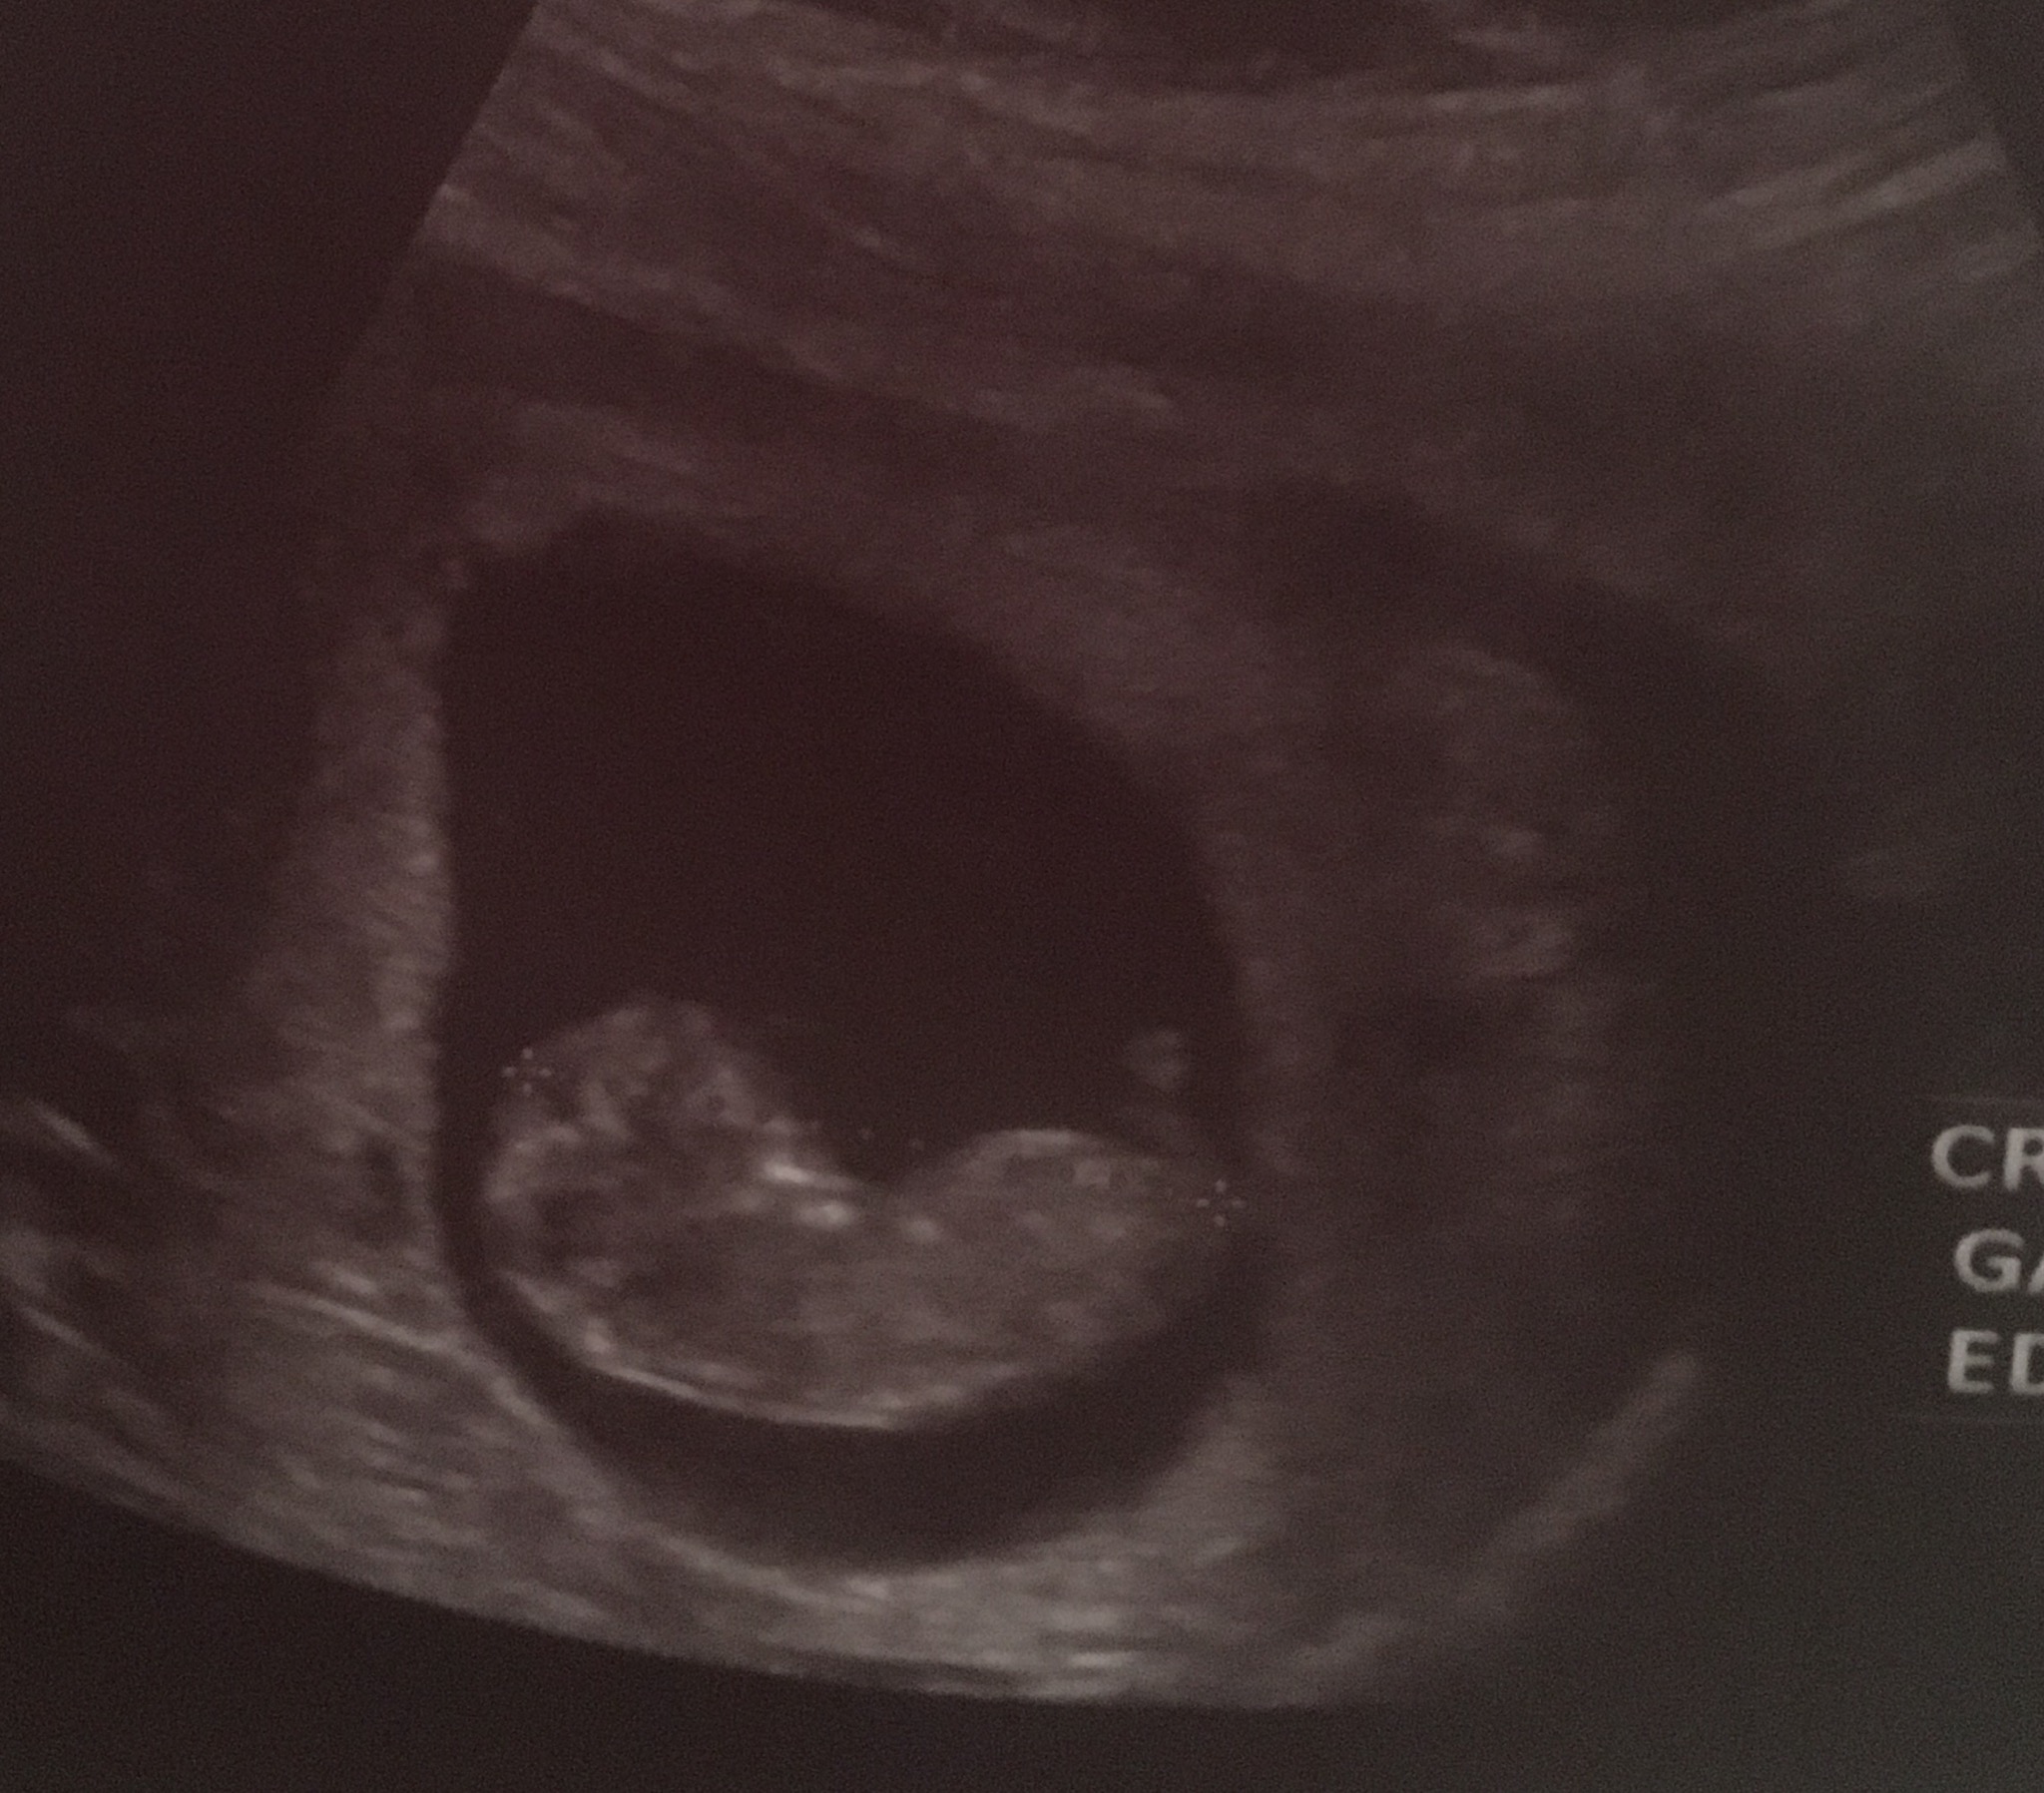

سلام دوستان گلم امروز سونو بودم گف ١٠ هفته و ٢ روز باردارم ولي جنسيتش معلوم نيست ميشه برام حدس بزنين ضربان قلبشم ١٦٦ هستش ممنونم ازتون